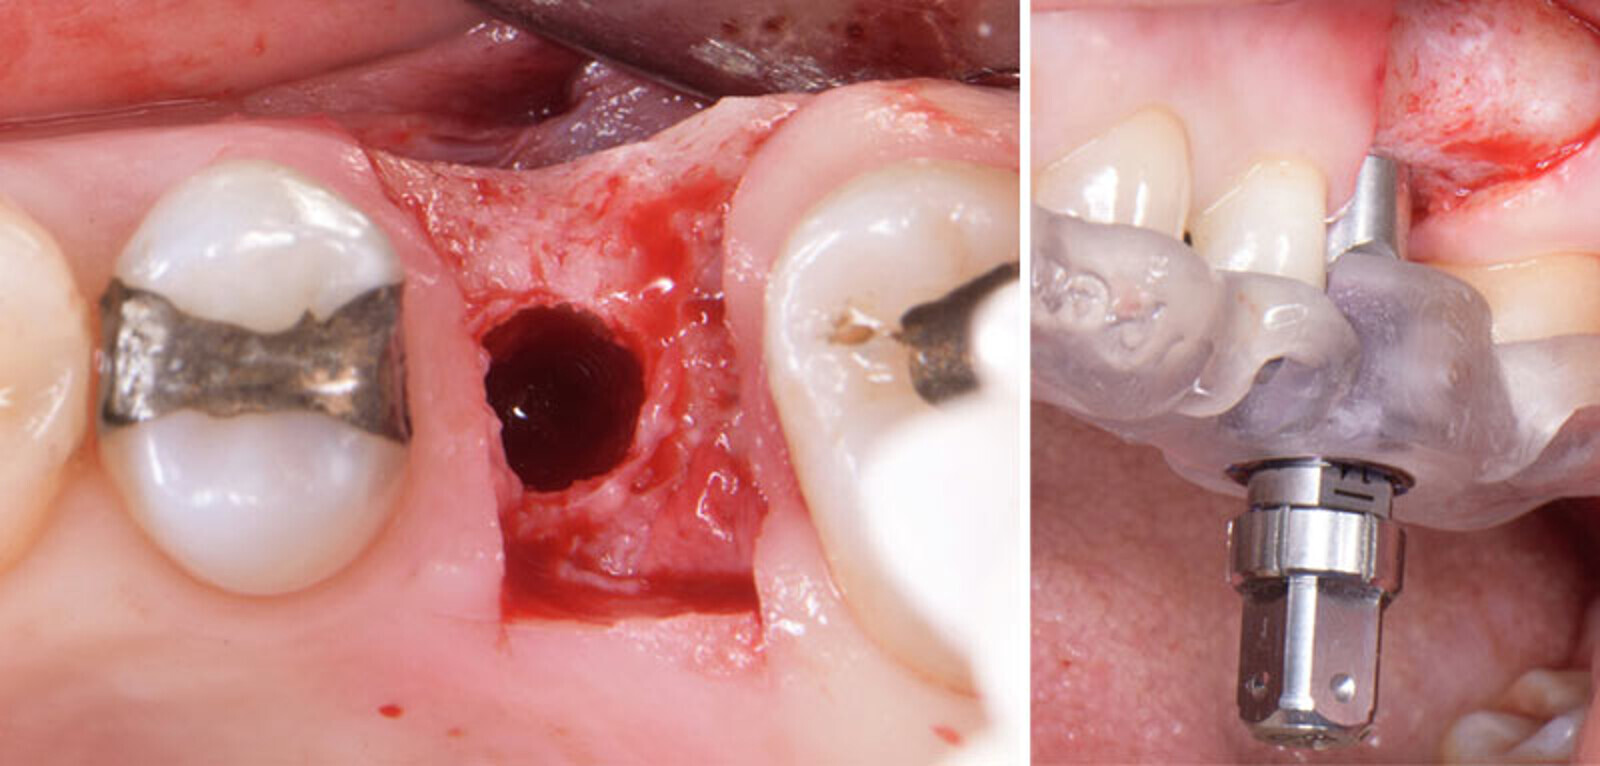

Buccal defect, need to raise a flap.

Site-specific papilla-sparing flap.

Buccal concavity.

Implant in place with the driver.

No implant threads exposed.

Grafted with EthOss. No membranes used.

Sutured with Vicryl 5-0.